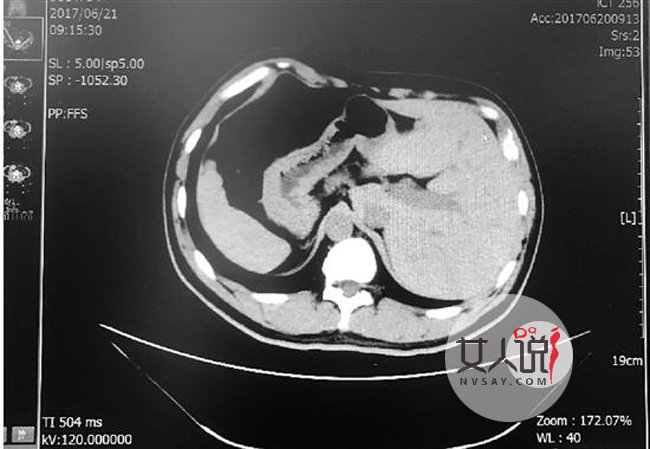

张先生今年41岁,家住温州市区,已经反复便血约十年,近两三个月出血突然增多。今年6月中旬,他来到温州医科大学附属第二医院(以下简称附二医)做检查。这一查,竟然查出了直肠癌,肿瘤的直径有5厘米左右,幸运的是还没有发生病灶转移,需要立即切除。

得知需要手术,张先生脱口而出的第一句话就是:“我是个镜面人。”这意味着,他的心、肝、脾等脏器都在与常人相反的位置,肠道也是如此。“一般人的大肠是顺时针的,阑尾在右侧,而镜面人的大肠是逆时针方向,阑尾在左侧。”